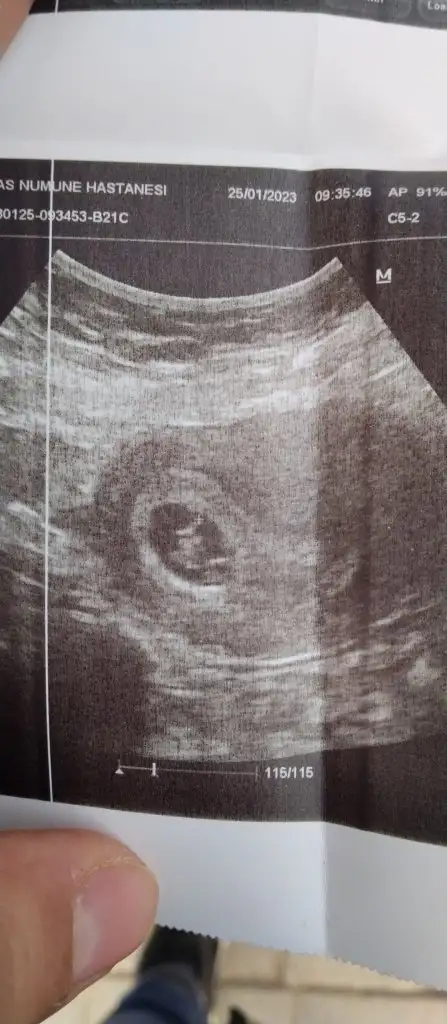

Bana mutlaka donus yp olur muO ilk fotoda gördüğün bacagın yansıması olabilir videosundan çekmiştim bunları durdurup durdurup:) Bakalım 18 inde göreceğiz

Videoda yakaladıgın fotoğrafın birinde bi cıkıntı var canım altta örnegini attım o cıkıntı düz geliyorsa kız diyolar seninde kız gibi benim bebeğimde de var doktor kız gibi ama yanılabilirim kesin olarak 18 subatta söylüycem dedi. Randevu günlerimiz aynı bende zor sabrediyorum suan